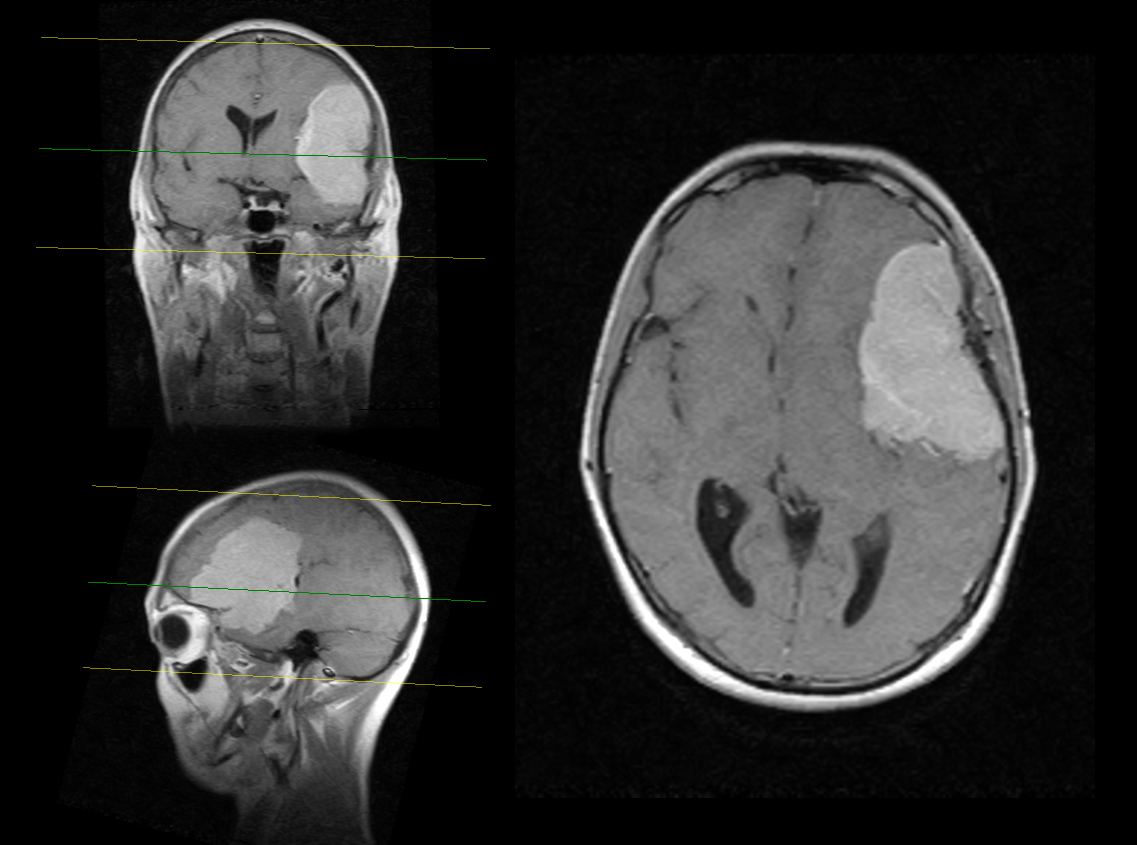

Пухлина

Ознаки зростаючого новоутворення в мозку: часті запаморочення з дзвоном у вухах, при цьому хворий перестає чути звуки з одного боку.

Нудота, відчуття млявості, супутні описаним станів, можуть говорити про великих розмірах пухлини, яка тисне на область, що відповідає за блювотний рефлекс. При злоякісних і доброякісних утвореннях під час сну з’являються пульсуючі болі в голові, які проходять після пробудження. При описаних станах проводять МРТ.